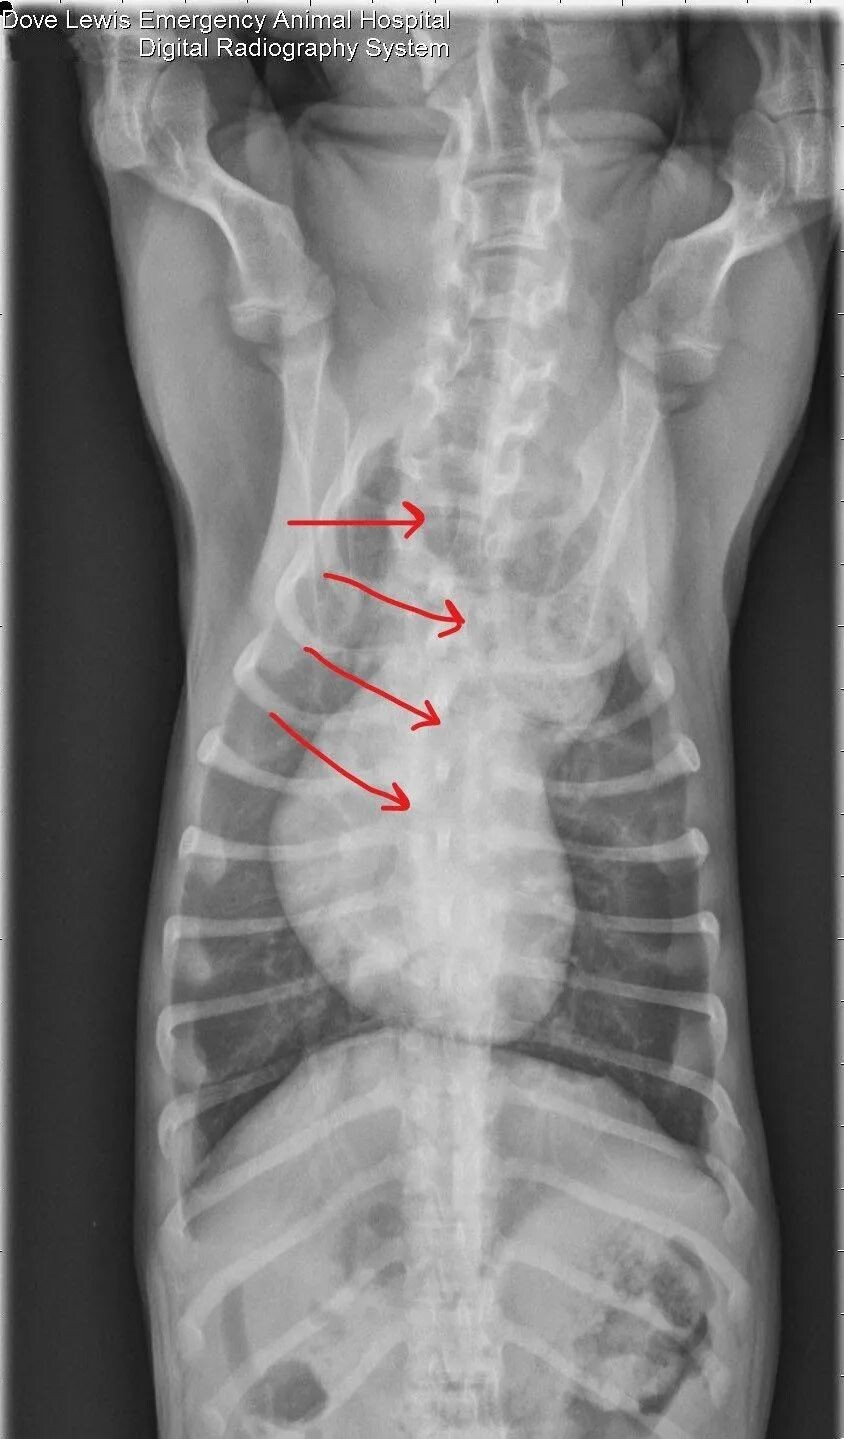

血管环是大血管的发育异常现象,导致食管和气管被完整或不完整的环状结构所包围。血管环畸形有几种类型,最常见的是持久性右主动脉弓与左肺动脉韧带。德国牧羊犬和爱尔兰赛特犬似乎是主要发病品种。动物在断奶前通常是正常的,在能进食固体食物后开始有返流症状。临床症状为进食后返流吐出未消化的食物,生长缓慢,虽然食欲良好但营养不良,呼吸道症状可能有吸入性肺炎。根据动物特征、病史、体格检查及放射 /CT 扫描或食管镜检查结果可做出诊断。胸部 X 线片可见心脏前方有扩张的食管,含有液体、空气或食物。心脏后方的食管通常是正常的。在腹背位正片中,气管有一处特征性的向左的弯曲,伴有局灶性狭窄(图 2)。由于食管扩张程度会随年龄增长而不断加重,长期用药通常是没有效果的。一般建议确诊后尽快手术治疗。虽然有些狗需要长期调整饮食,但大多数病例预后是良好甚至极佳。

图 2